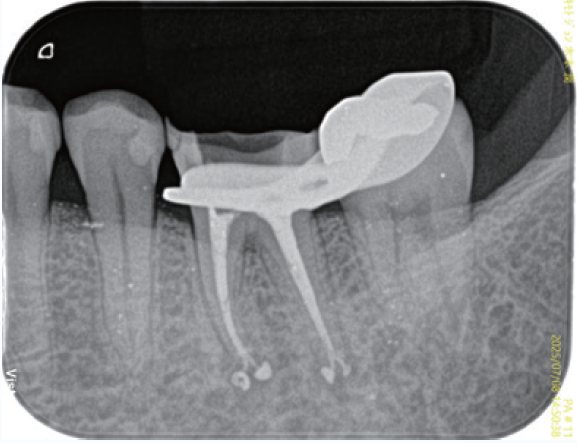

「臨床症例2」複雑な湾曲を有する根管に対して対処したケース

●年齢50代 男性

咬合による歯冠破折から歯髄炎になり、根管処置が必要となる。器具操作が困難なため、紹介を受け当院を受診。近心頬側根管は根管口付近は狭窄を呈し、遠心方向に向けて開口しており、近心頬側根管の器具の挿入はかなり遠心方向から器具を回し込む必要があった。また根尖の開口部は近心方向にあり、根管の全体的な形態はS字のような形態を有する。全体的に湾曲度を緩やかになるよう処置を進めた。器具の選択に関しては、より柔軟性のあるマルテンサイトのニッケルチタンファイルを選択した。根管口付近の形態修正は器具が歯軸に対して極力平行になるように行なった。EMR時のレントゲン像では、3根管それぞれが歯軸に対してほぼ平行に挿入されていることが確認できる。しかしながら根尖部付近がそれぞれ大小の湾曲を有し、特に近心頬側根は近心方向に湾曲している。根管上部の形態修正とマルテンサイトのファイルの使用によって根尖への器具の到達に成功した。根管充填はウォームドガッタパーチャとMTAシーラーを用いセクショナル法で行った。術後4年弱のレントゲン像で、根尖周囲の歯周組織は安定していることが確認できる。

① 初診時(2021/06/21)

口蓋根根尖部には炎症による歯根膜腔の拡大が見られる

②EMR測定時

根管口付近の修正形成を行い、ファイルが歯軸に対して平行に入ることによって根尖部の湾曲に対してニッケルチタンファイルがその特性を活かし、元々の根管形態を崩さず追従し根尖部への到達を獲得できている

③根管充填時

それぞれの根の根尖部に根管充填材が到達していることが確認できる

近心頬側根根管は根尖部は近心方向に湾曲して開口しているのが確認できる

④補綴装置装着時

根管処置後臨床症状もなくレントゲン所見も安定している

⑤術後4年弱(2025/05/28)

臨床症状もなく経過良好であり、初診時に見られた口蓋根根尖部の歯根膜腔の拡大も改善し安定している